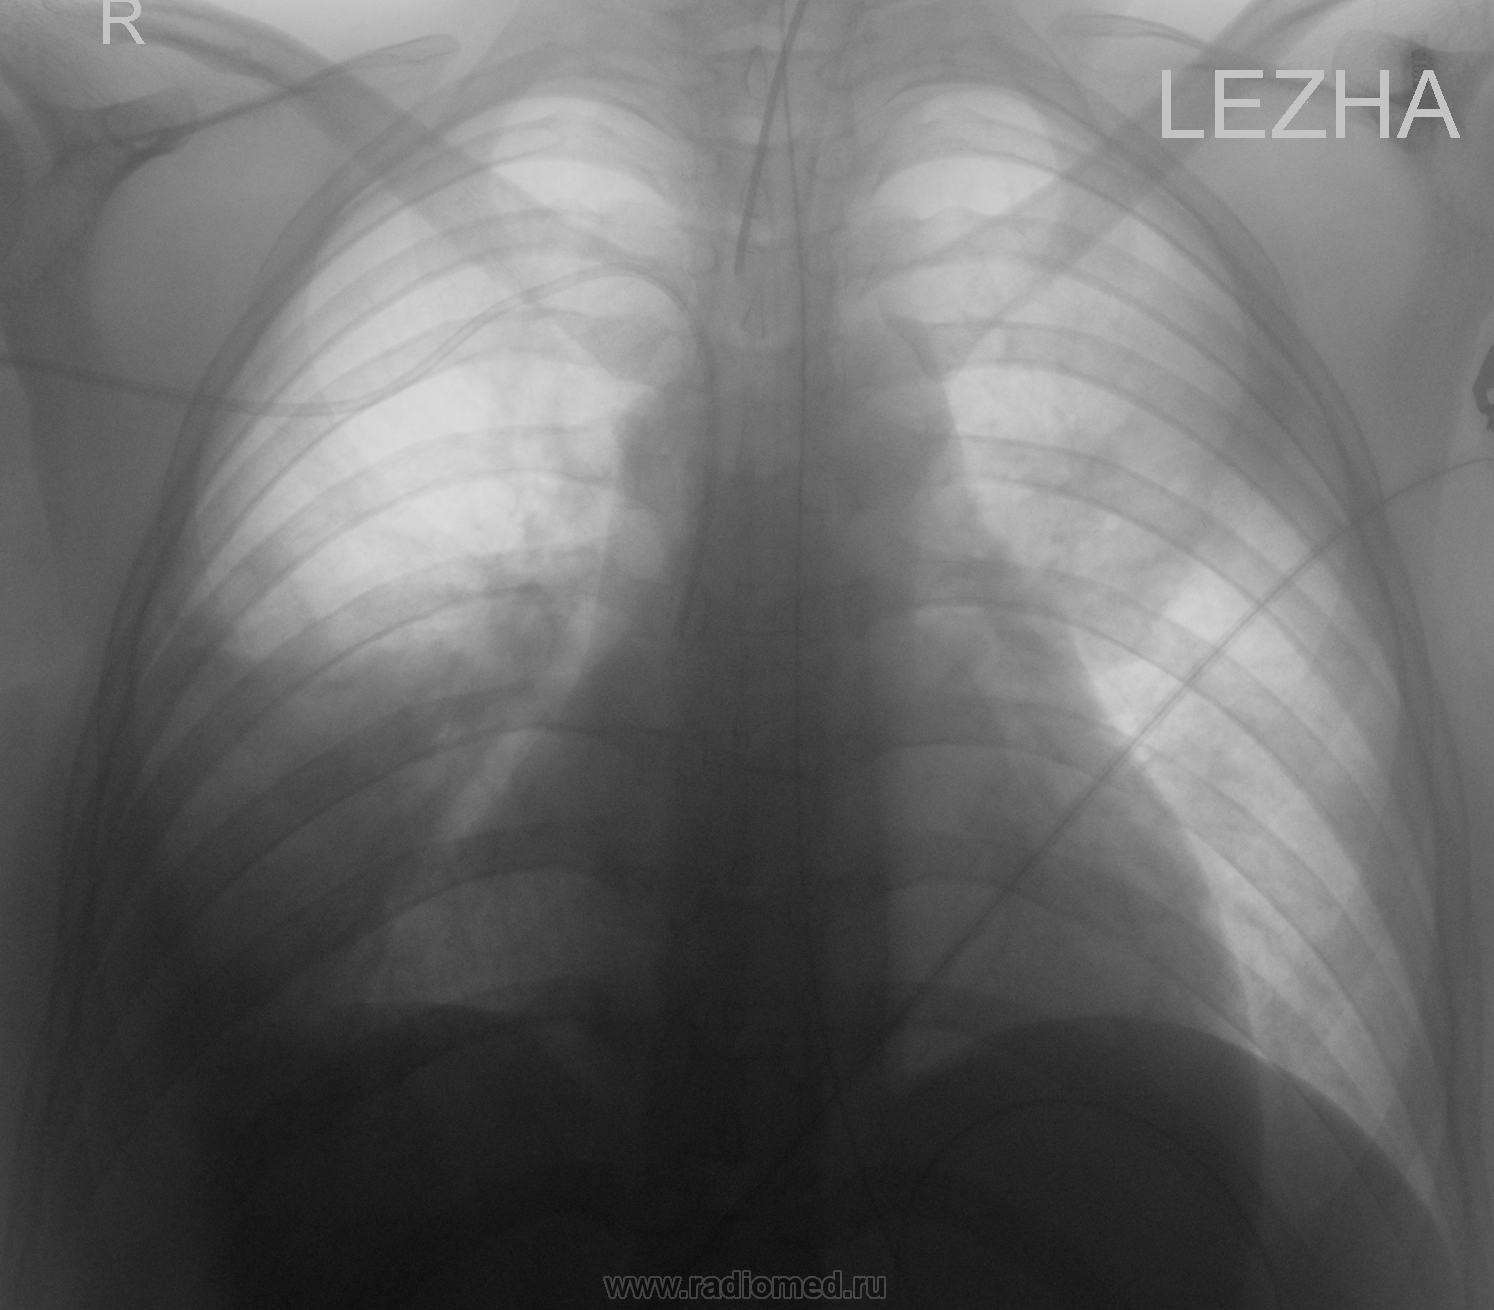

Пол пациента: Женский пол Тип патологии: Инфекция Область исследования: Грудная клетка и верхние дыхательные пути Методы исследования: Rg Вот и до нас докатилась волна Гриппа А (H1N1) : Сегодня пришёл результат ПЦР. Девушка 20 лет находиться в тяжелом состоянии. Tue, 22/12/2009 - 15:32 #1 Anny Offline Last seen: 11 years 8 months ago Joined: 18.09.2009 - 15:59 Posts: 45 Скажите вы откуда? И есть ли у девушки сопутствующая патология? Wed, 23/12/2009 - 18:40 #2 v1tal Offline Last seen: 4 years 10 months ago Joined: 07.06.2008 - 19:41 Posts: 1779 Девушка была на сроке беременности 38-39 недель, после консилиума было проведено кесарево сечение, с ребёнком всё хорошо, а вот девушка пока на ИВЛ. "Знаешь, у некоторых врачей есть комплекс мессии — им необходимо спасать мир. А у тебя комплекс Рубика — тебе необходимо решать головоломки." Wed, 23/12/2009 - 18:56 #3 Anny Offline Last seen: 11 years 8 months ago Joined: 18.09.2009 - 15:59 Posts: 45 Жалко девушку. Но теперь понятно почему такая пневмония. Будем надеяться что все обойдется.

Девушка была на сроке беременности 38-39 недель, после консилиума было проведено кесарево сечение, с ребёнком всё хорошо, а вот девушка пока на ИВЛ.

Жалко девушку. Но теперь понятно почему такая пневмония. Будем надеяться что все обойдется.